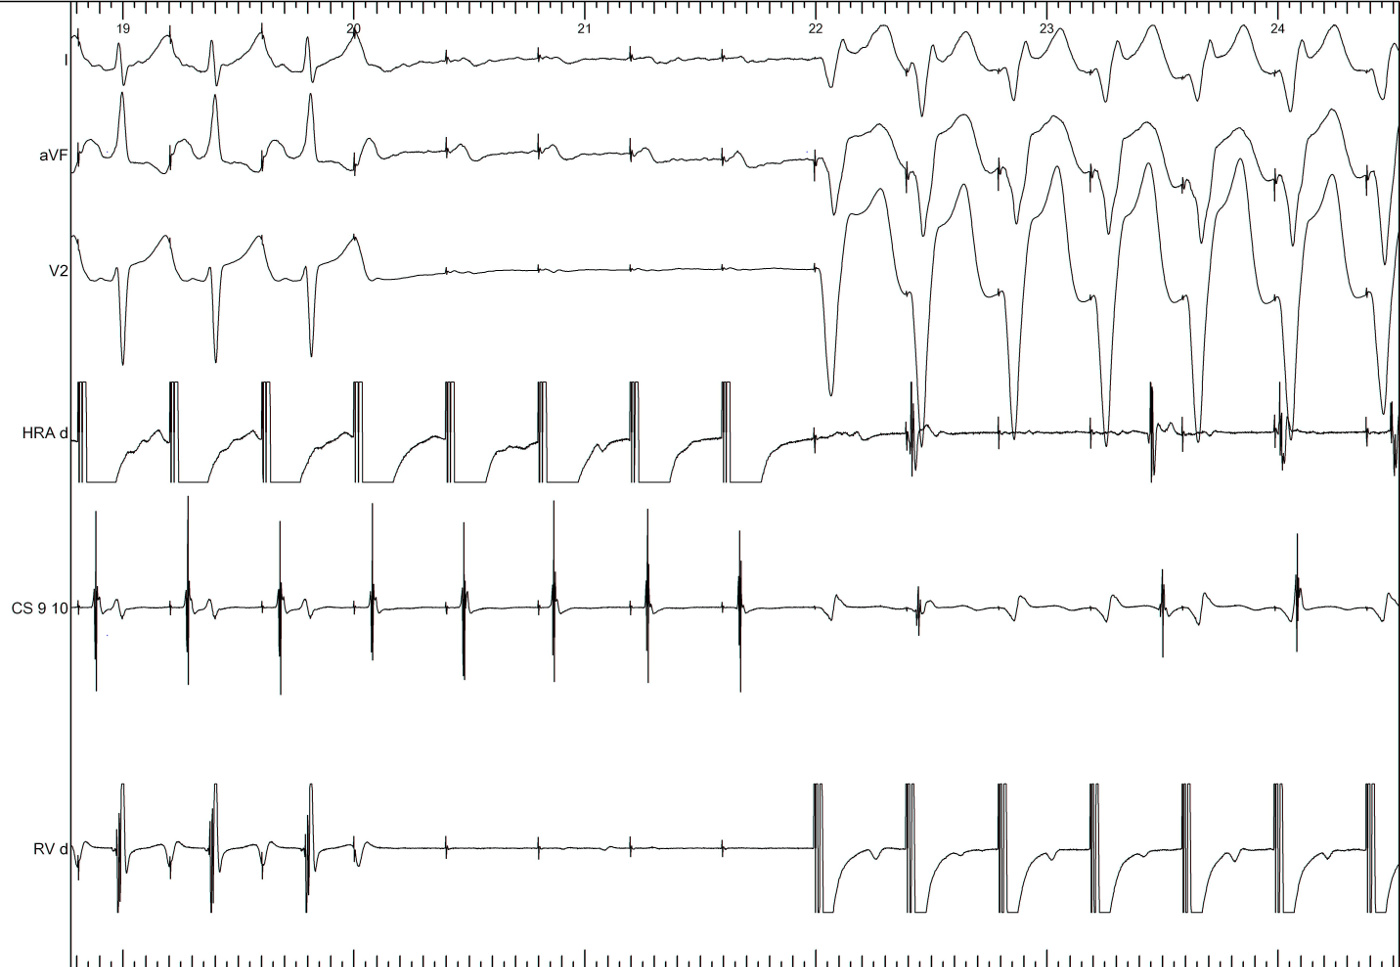

RV overdrive pacing - most useful maneuver

• Easy to perform and interpret

• Can distinguish AT from AVNRT / AVRT (VAAV versus VAV)

• Can distinguish between AVNRT / AVRT (cPPI-TCL, SA-VA)

• Onset of entrainment can provide clues

• Can help even if not entrained !

RV pacing in narrow QRS tachycardia - Rule out (or in) AT

vav.jpg

vav_measurements_atrium_entrain.jpg

RV pacing in AT - VAAV

VAAV.jpg

RV pacing in narrow QRS tachycardia - AVNRT / AVRT

vav_measurements_ppi.jpg